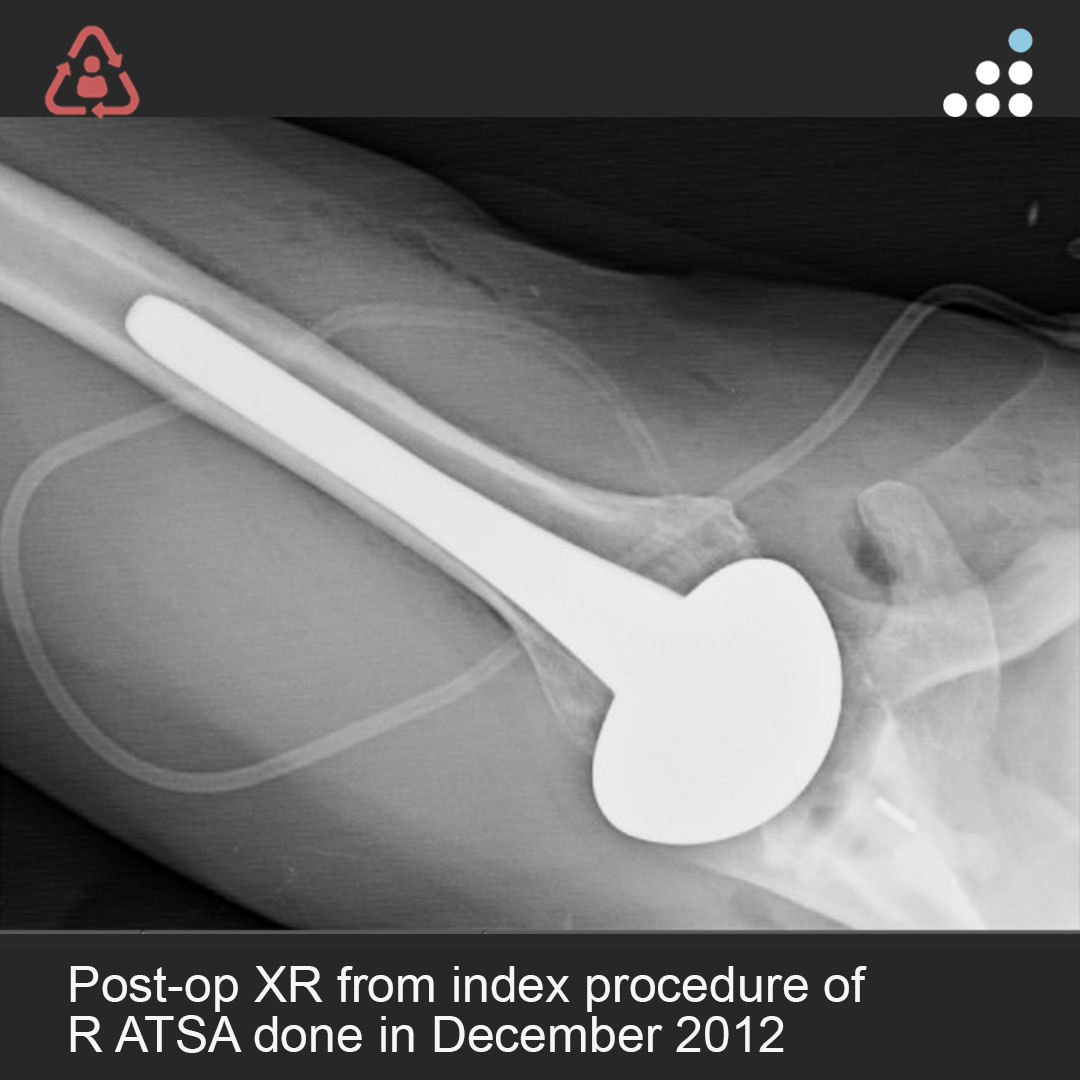

@orthobullets @KPSCALnews @rkh_md @DrMarecek @DeformityDoc @jamesablairMD @FractureDoc @stevemchale @traumaticum @DrFraneNicholas I am concerned about the +Fleck/flake sign. Get MRI or ultrasound to rule out a triceps rupture. If torn, I would perform ORIF and Triceps repair, after restoring the underlying metabolic issues. If the triceps is not torn, then would treat non-operatively.